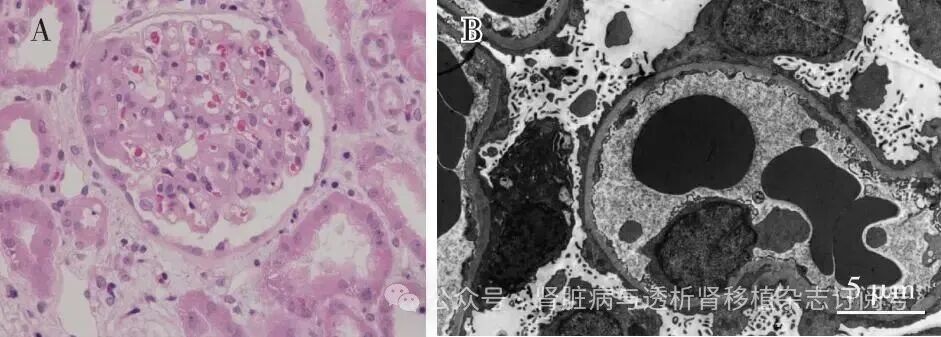

肾活检光镜下31个肾小球中12个节段硬化(图1A),肾小管间质中度急性病变,多灶性肾小管上皮细胞扁平、刷状缘脱落,管腔内见较多蛋白管型及多处嗜碱性钙盐沉积。电镜下观察的肾小球基膜厚300~580 nm,系膜区、基膜内皮下、上皮侧均未见电子致密物分布,肾小球足细胞足突广泛融合(>90%),胞质少量微绒毛化(图1B),近端肾小管上皮细胞刷状缘脱落。免疫荧光染色均阴性。

图1 A:肾小球节段袢皱缩扭曲,与囊壁粘连,周围足细胞增生、肿胀(HE,×400);B:肾小球足细胞足突广泛融合(>90%),胞质少量微绒毛化(EM)